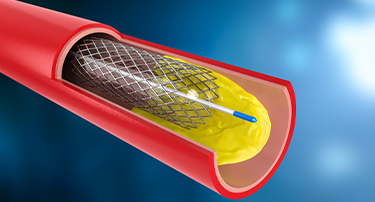

Heart bypass surgery is a type of surgery that creates a new path for blood to flow when your heart’s arteries are blocked. Cardiologists usually take a healthy blood vessel from your chest or leg and connect it around the blocked artery.

A Complete Guide to Heart Bypass Surgery: Why It’s Done, How It Works & What to Expect

Heart bypass surgery, or coronary artery bypass grafting (CABG), is a life-saving surgery that is done to enhance the flow of blood to the heart when the coronary arteries are blocked or narrowed very much. Such a condition, or coronary artery disease (CAD), may result in chest pain (angina), shortness of breath, and a higher risk of heart attacks.

Heart Bypass Surgery: Purpose, Procedure, Risks And Recovery

Heart bypass surgery, also called CABG, is a critical surgical procedure used to ensure adequate blood flow to the heart when the coronary arteries have blockages or are narrowed with coronary artery disease (CAD). Blockages in the coronary arteries reduce the oxygen supply to the heart. This can result in chest pain and shortness of breath, and may even lead to heart attacks, which can be fatal. This surgical procedure is often recommended when lifestyle modification, drugs, or other minimally invasive treatments do not respond to the condition.

Is Cardiac Surgery Right for You?

It's not always necessary to have surgery for cardiac issues. Medication, lifestyle modifications, or nonsurgical procedures can sometimes be used to treat them. By using energy, for instance, catheter ablation can stop abnormal electrical signals from passing through your heart by creating tiny scars in the tissue surrounding it. Through a minimally invasive procedure called coronary angioplasty, a blocked or narrowed coronary artery is kept open by the insertion of a stent.

What is Coronary Heart Disease?

Cardiovascular disease is a group of diseases that affect the structure and functioning of heart and blood vessels. These diseases can affect one or many parts of your heart and/or blood vessels. Globally, coronary heart disease (CHD) is a leading cause of both fatalities and disabilities. In 2005, a World Health Organisation (WHO) report stated that 17.5 million deaths (30%) globally were attributed to cardiovascular disease (CVD).